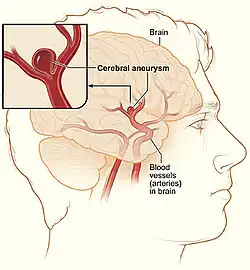

An aneurysm is an abnormal bulging of small sections of arteries, which increases the risk of artery rupture. Intracranial aneurysms are a leading cause of subarachnoid hemorrhage, or bleeding around the brain within the subarachnoid space. There are various hereditary disorders associated with intracranial aneurysms, such as Ehlers-Danlos syndrome, autosomal dominant polycystic kidney disease, and familial hyperaldosteronism type I.[27][28][29] However, individuals without these disorders may also obtain aneurysms. The American Heart Association and American Stroke Association recommend controlling modifiable risk factors including smoking and hypertension.[30]